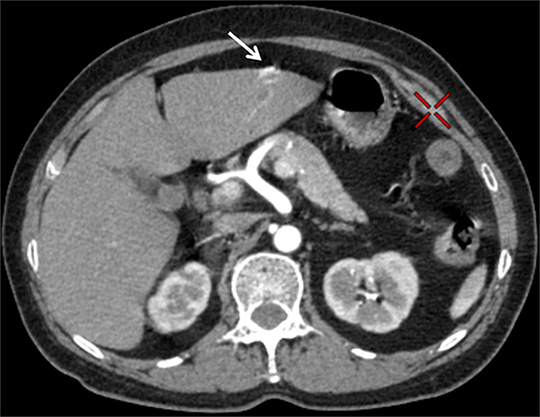

病例点评及临床价值: 常规CT增强扫描,病灶有无强化直接影响病变的定性诊断,然而血肿、钙化在CT图像上亦呈高密度影,难以辨别,往往需要多期扫描,甚至追加平扫来加以鉴别、区分,增加患者辐射剂量。

能谱CT扫描能够获得各种基物质图像,在一期扫描中对病灶强化、血肿、钙化加以区分,满足病变定性需求,同时降低患者辐射剂量。

利用Water/Iodine基物质图像区分增强和血肿 利用Calcium./Iodine基物质图像区分钙化和增强 利用Water/Calcium基物质图像区分钙化和血肿